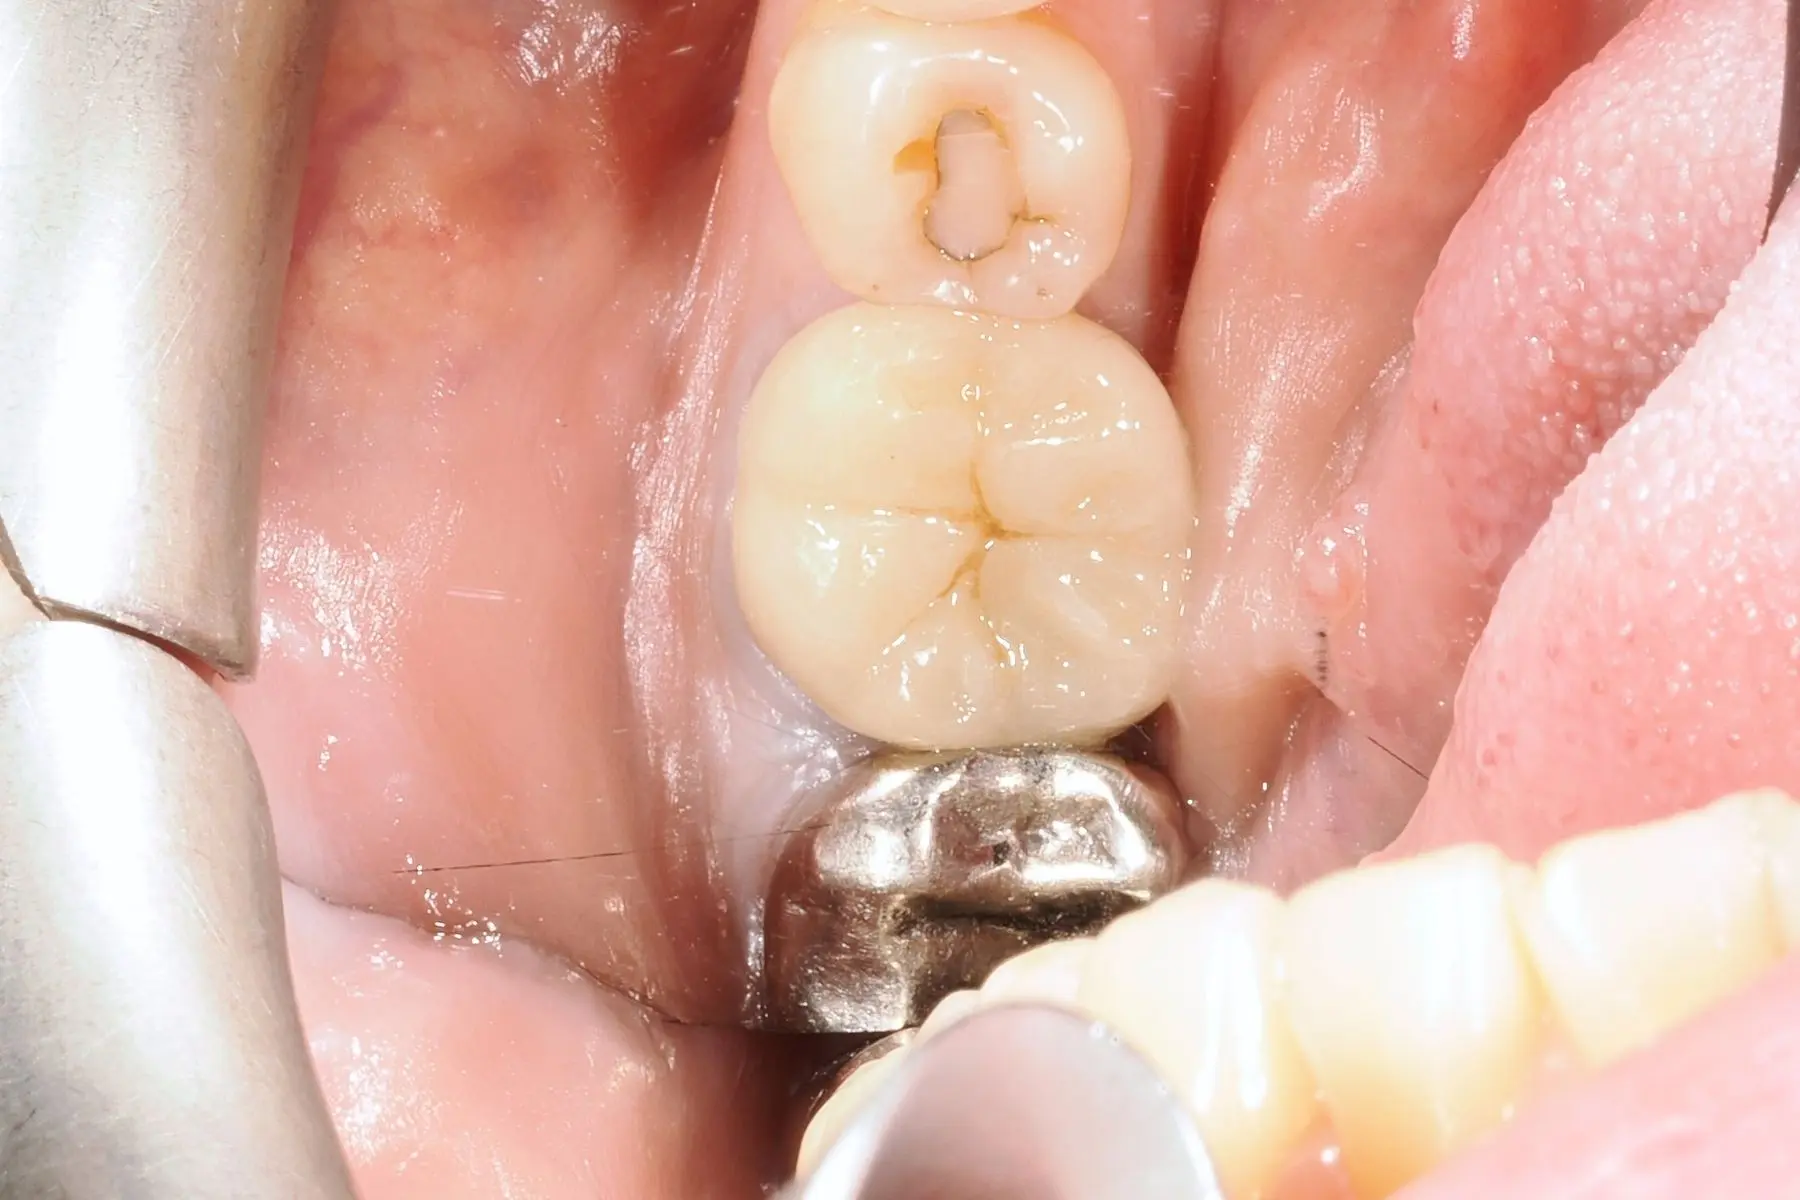

• 術前 41

術後 39

3D齒雕

主治醫師

• 陳暐文

治療時間

約1個月

主訴

左下牙齒補的地方掉落